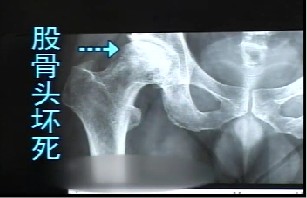

腓骨移植治疗股骨头坏死